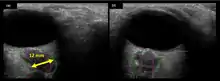

The astronauts afflicted with long term visual changes and prolonged intracranial hypertension have all been male, and SOS may explain this because in men, the sternocleidomastoid muscle is typically thicker than in women and may contribute to more compression. The reason that SOS does not occur in all individuals may be related to anatomic variations in the internal jugular vein. Ultrasound study has shown that in some individuals, the internal jugular vein is located in a more lateral position to Zone I compression, and therefore not as much compression will occur, allowing continued blood flow.